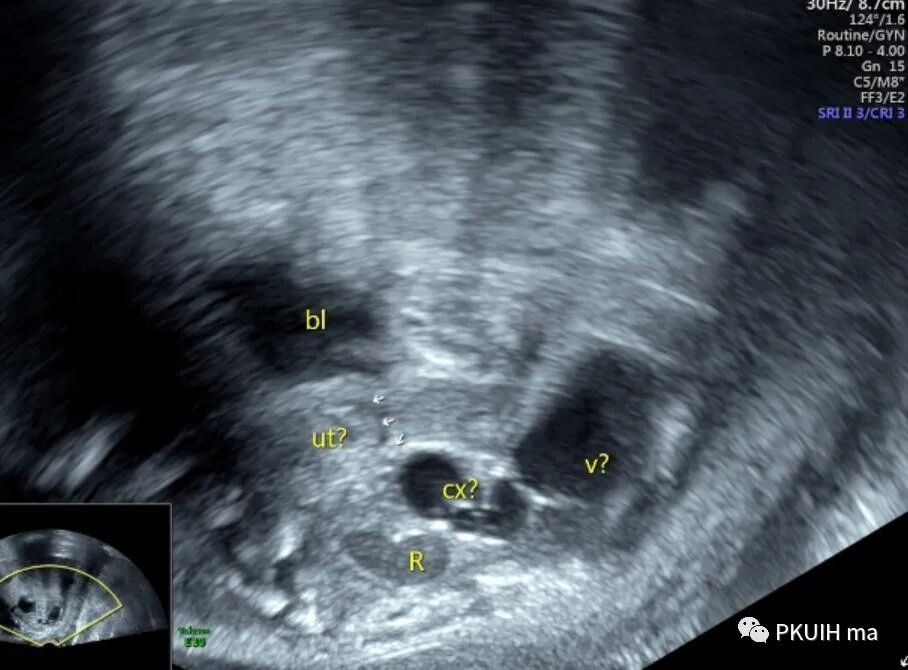

外院孕妇孕31周以骶尾部前方囊实性包块考虑畸胎瘤转诊,我院超声检查如下:

胎儿骶尾部结构清晰、未见明确占位性病变

超声显示外生殖器为女性特征,肛门前方见囊性回声,冠状切面显示囊性回声延至会阴处

囊性回声似呈葫芦状,下方大,上方小

胎儿臀位,改用经阴道超声检查,囊性包块边界清晰,与周围组织分界清。

结合以上图像考虑为处女膜闭锁合并阴道积液,由于包块不规则不能除外合并阴道斜隔等其他异常。